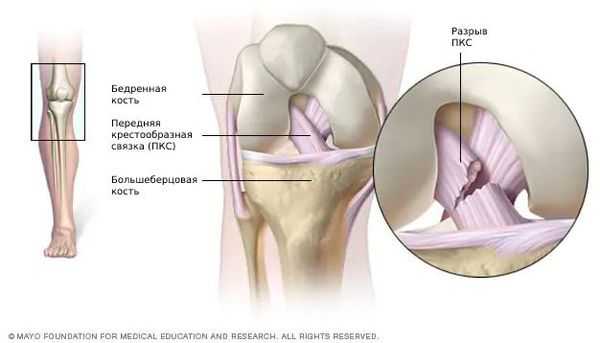

Разрыв передней крестообразной связки (anterior cruciate ligament injury) — это одна из самых тяжёлых травм коленного сустава. Повреждение сопровождается щелчком в колене и невозможностью продолжать физическую активность. Затем появляется отёк и становится трудно сгибать и разгибать ногу в суставе.

![Разрыв передней крестообразной связки [13]](/pimg3/priznaki-vertikalnogo-prodolnogo-B77F.jpg)